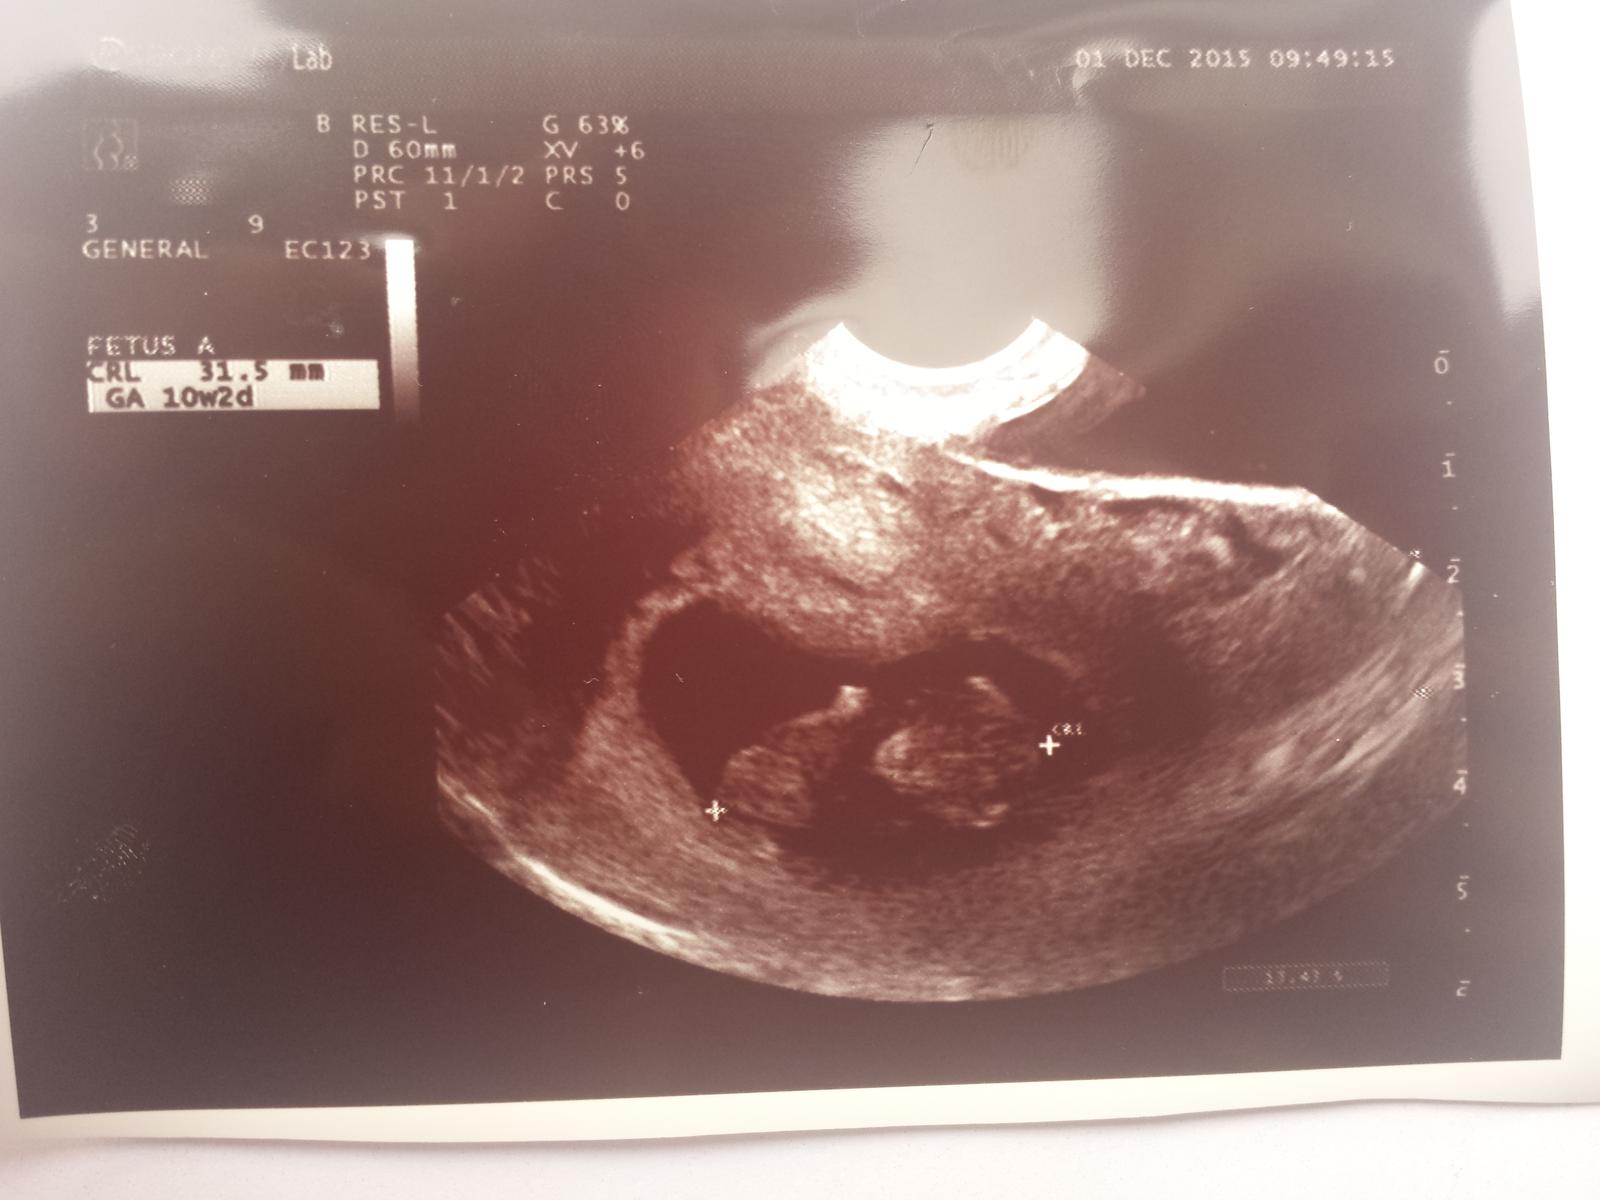

Ahojte babulky tak ja sa hlasim po dnesnej kontrole, vsetko je v poriadku babenko rastie ako z vody dokonca sme o tyzden vacsi ako mi to vychadza podla poslednej ms...cize uz som v 10+2tt  A kedze 12.tt je uz na dosah tak mi dnes ani nerobila odbery ziadne ale az buduci utorok ze uz komplet vybavime vsetko  Tesiiiim sa velmiiiiii

@nicolettka2126 blahozelam krasne foto uplne super tesim sa a kolko merate?♡ Som rada ze vsetko ide ako maaaa a kedy mas dalsie sono?

@badimeria dakujem pekne 🙂 Meriame 3,15cm a pritom pred 4tyzdnami sme mali iba 4mm takze krasne drobec narastol...uplne som soknuta ze je este aj tyzden popredu 🙂